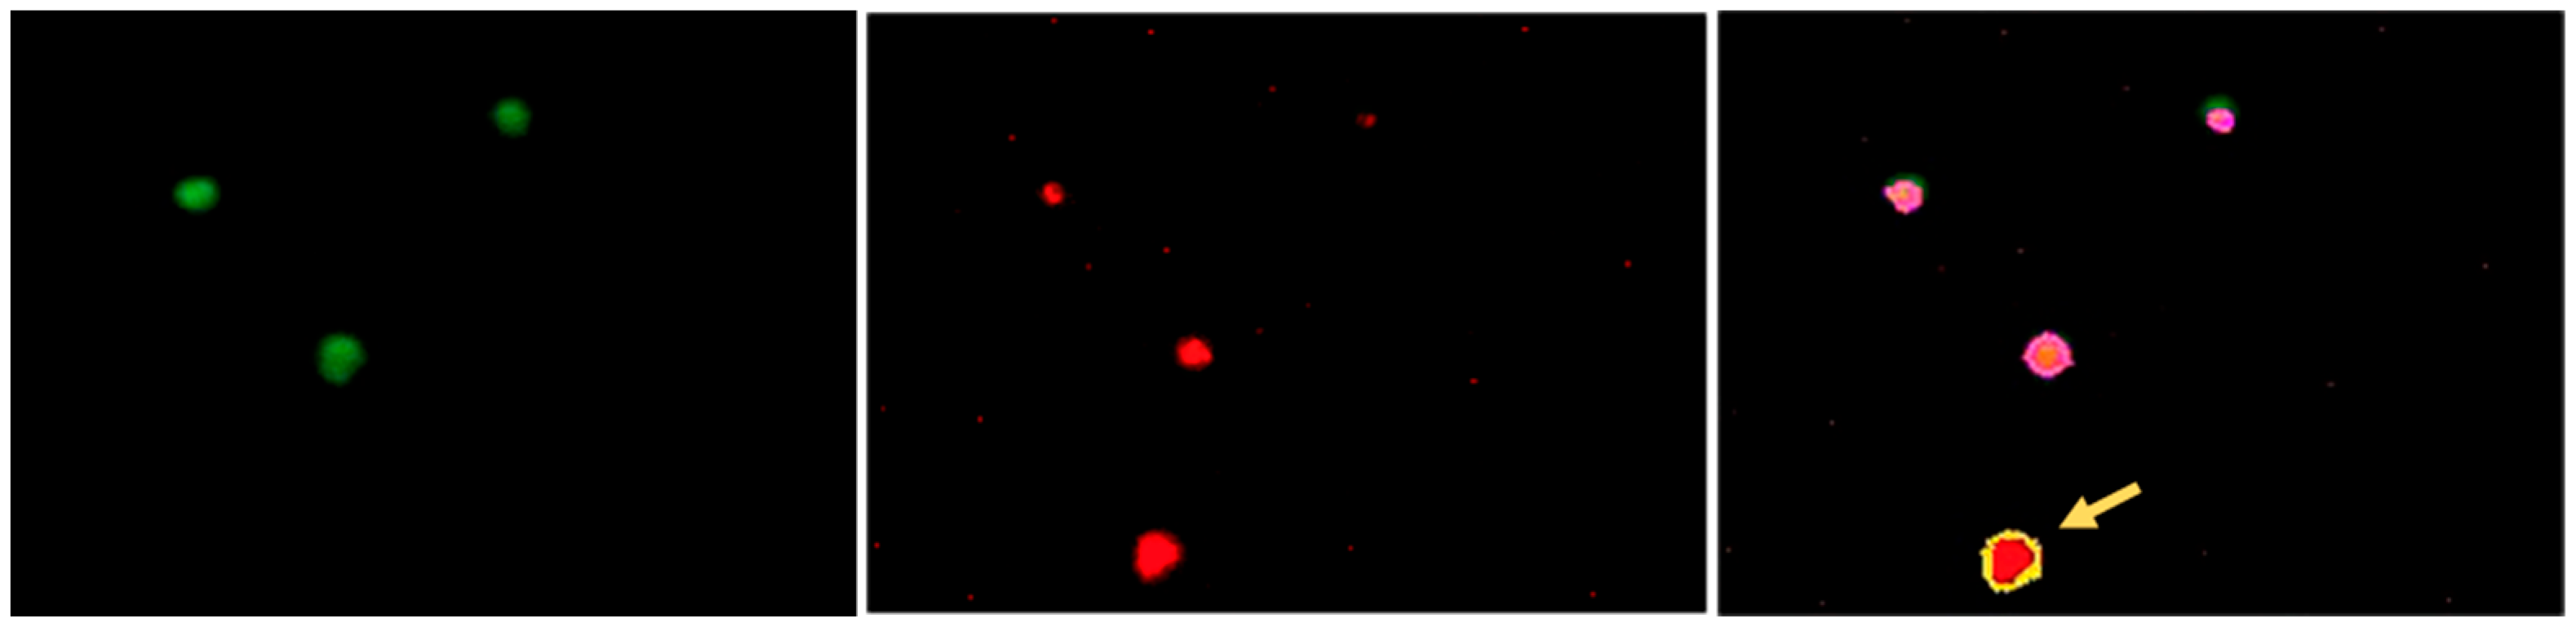

3.2. Establishing the Parameters for Automated Assessment of the Platelets

3.3. Quantitative Image-Based Confirmation of BSS and GT Diagnosis on IF-Stained Blood Smears